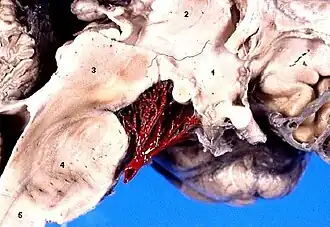

1:Hipotálamo. 2:Tálamo. 3:Mesencéfalo. 4:Protuberancia. 5:Médula espinal.

Vista inferior del encéfalo humano. Es visible el surco basilar (#8), por el que discurren la arteria basilar y la vena basilar.